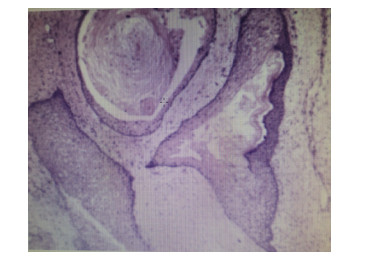

1 资料与方法患者,女,33岁,因“急起胡言乱语、行为异常10 d”于2019年4月21日收治于杭州市第七人民医院。4月11日患者因工作压力大在单位突然情绪崩溃,胡言乱语,行为异常,后回家休息。在家中,患者间歇性通过哭泣、叫喊发泄情绪,彻夜不眠,大声咒骂,情绪异常激动,送至杭州市第七人民医院住院治疗。入院后查血常规、生化全套、甲状腺功能、头颅CT等无异常,诊断考虑:焦虑状态、精神障碍、分离转换障碍,给予奥氮平、丙戊酸钠、百忧解等药治疗,效果不佳。5月3日患者突然发热,体温最高达39.1℃,急查血常规:白细胞11.44×109/L,中性粒细胞8.32×109/L,C反应蛋白229.2 mg/L。生化:谷丙转氨酶143.8 U/L,谷草转氨酶78.9 U/L,肺CT示左肺上叶舌段及右肺中叶内侧段慢性炎症或纤维灶考虑。予头孢呋辛抗感染治疗,效果不佳。追问病史,患者诉7年前体检发现畸胎瘤,直径约2.7 cm,无不适,未治疗,后育二女,均无异常。急查腹部CT示:下腹部盆腔内巨大占位,肿瘤首先考虑,畸胎瘤可能性大:右侧附件区低密度灶; 盆腔少量积液。因患者感染控制不理想,精神症状稍好转,遂出院。至本地某三甲医院就诊,复查血常规:白细胞15.9×109/L,中性粒细胞12.62×109/L,C反应蛋白239.4 mg/L。生化:谷丙转氨酶117 U/L,谷草转氨酶69 U/L。凝血酶原时间14.6 s,D-二聚体5 520 μg/L。予头孢类抗生素静滴,体温控制不佳,并出现腹部绞痛。为求进一步诊治于2019年5月13日以“发热待查”入树兰医院感染科。患者入院后仍反复高热,炎症指标高,全腹平扫+增强CT示:双附件区及下腹腔多发占位,考虑多发畸胎瘤,较大病灶破裂可能,腹盆腔积液(图 1),头颅MRI无异常。5月16日组织感染科、胃肠外科、妇科、精神科等多学科会诊(MDT)。感染科认为患者目前双侧畸胎瘤伴破裂,腹腔继发感染明确,曾有精神神经症状,故尚需排除脑炎; 胃肠外科认为患者目前盆腔肿块卵巢肿瘤诊断明确,建议:⑴先确定脑炎与肿瘤的关系; ⑵手术治疗; ⑶若同结肠有关,术中同时处理。精神科认为患者短期出现言行异常、情绪不稳定、遗忘、烦躁等多种精神症状,在杭州市第七人民医院住院治疗期间,又出现了高热、意识障碍、痫性发作等情况,起病急,精神症状变化快,考虑患者精神症状可能与畸胎瘤有关,建议完善腰穿检查,排除自身免疫性脑炎(NMDA抗体)所致精神障碍。妇科认为患者已婚育,发现畸胎瘤7年,突发腹痛、精神症状、发热等,CT提示盆腔巨大包块,不排除畸胎瘤破裂感染粘连可能,建议:⑴患者目前不排除畸胎瘤与精神症状、自身免疫性脑炎相关,故完善NMDA抗体检测,如能明确则行双侧切除,术后相关激素替代治疗,如非自身免疫性脑炎,则术中尽可能保留卵巢功能。⑵控制感染,完善检查后转妇科手术治疗。5月19日查腰穿结果提示:脑脊液抗谷氨酸受体(NMDA型)抗体IgG+ 1∶10,诊断自身免疫性脑病明确,考虑患者精神症状与畸胎瘤关系密切,且畸胎瘤较前进展快,恶变可能,局部小破裂,腹腔感染明确。在感染科予抗炎、护肝、抗精神病等治疗后患者病情有所控制,5月21日转妇科进一步诊治。完善术前准备,于5月28日行“腹腔镜下双侧卵巢囊肿剥除术+左侧输卵管切除术+盆腔粘连分离术+肠粘连松解术”,术中见子宫前位,正常大,表面光滑,形态正常; 左侧卵巢冠囊肿增大约10 cm×11 cm×9 cm,与左输卵管一起顺时针扭转1.5圈,左侧输卵管增粗水肿。大网膜、乙状结肠和左侧卵巢冠囊肿致密粘连; 右侧卵巢分别见大小约3 cm×2 cm及2 cm×2 cm囊肿,右侧输卵管外观无殊。术中及术后病理均提示:⑴(左卵巢)成熟性畸胎瘤伴神经组织及坏死; ⑵(右卵巢)成熟性畸胎瘤(图 2)伴甲状腺肿。术后4 d,复查血常规+超敏C反应蛋白,白细胞计数3.7×109/L,中性粒细胞百分比58.8%,超敏C反应蛋白8.2 mg/L,患者恢复良好,停用抗生素。精神科会诊患者精神症状完全消失,接触交谈如常人。出院后随访:患者出院后未再服用精神类药物,继续免疫治疗[3]。随访1年,患者无明显精神症状,工作生活如常人。

| 图 2 患者2019-06-04术后病理结果(示成熟性畸胎瘤,HE×40) |